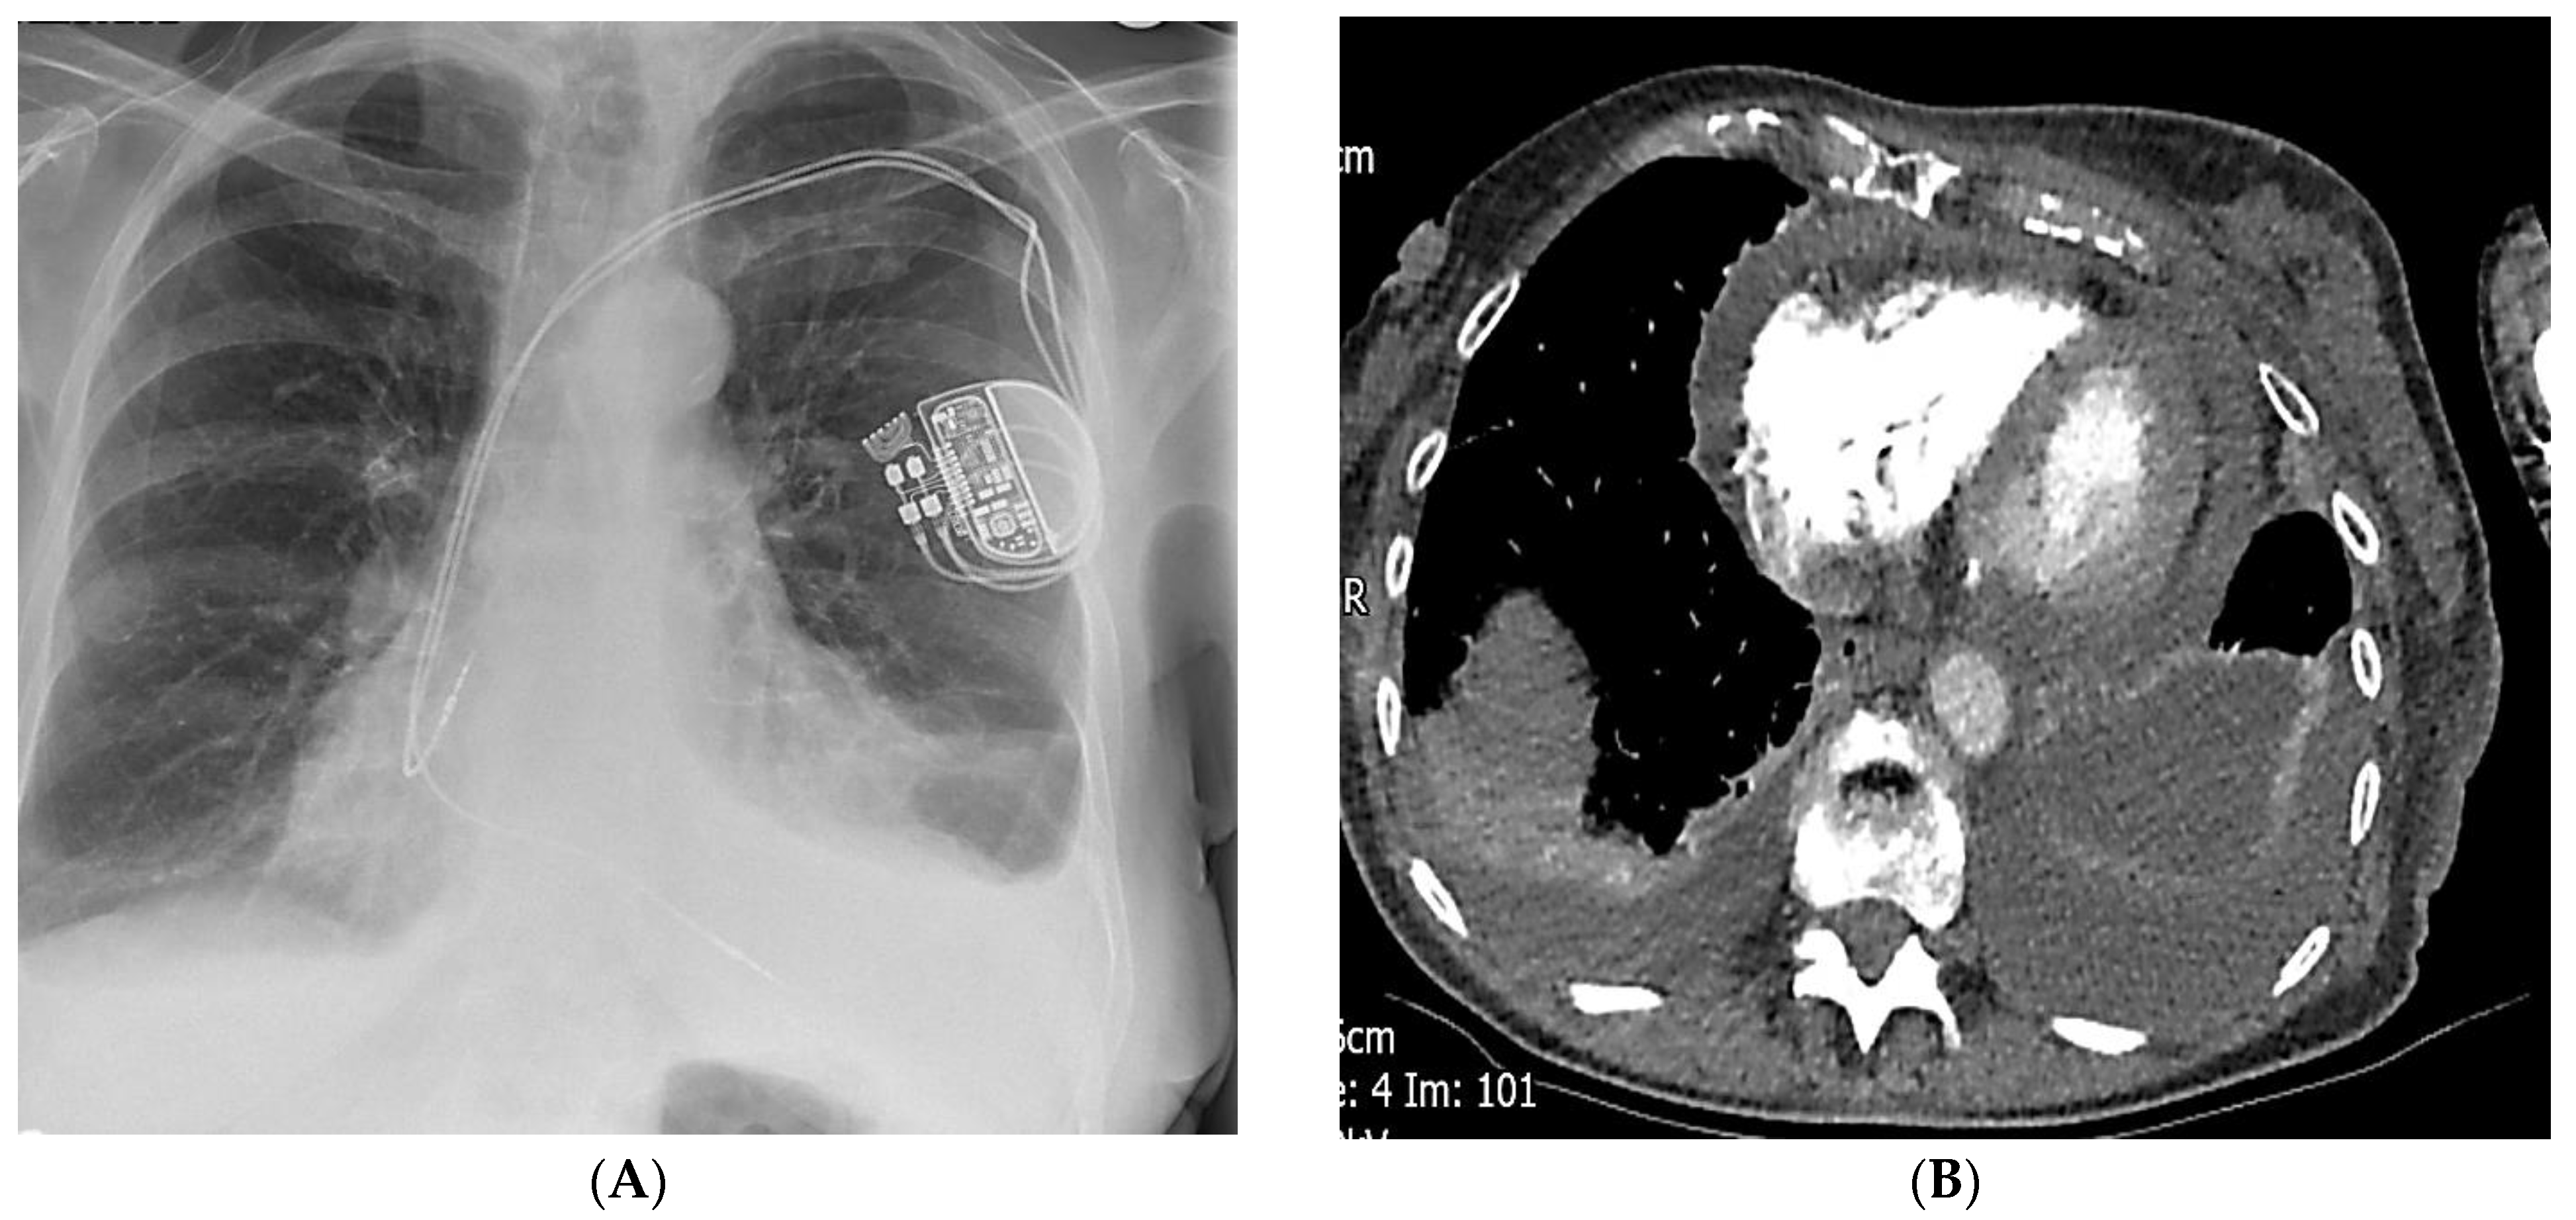

Dual Chamber Pacemaker Implant in Coronary Sinus Leading to Several Complications